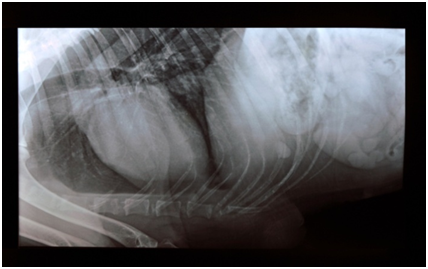

History revealed that these tumours developed vigorously within a very short period of time. In five animals (all were Spitz), the tumour masses were generally smooth to slightly nodular surface, non-ulcerated, pinkish to red in colour and originating from the gum (Figures 1A−1E), whereas in one animal (Labrador) tumour mass was diffused, ulcerated, areas of necrosis and originating from periodontal ligament in lower jaw (Figure 1F). The size of each tumour mass was measured by Vernier caliper and diameter was ranged in between 5-12 cm. Radiological examination revealed distant pulmonary metastases in one animal (Figure 3A). In this case, extensive destruction of bone with displacement of adjacent teeth was also observed (Figure 3B). All the cases that underwent cryosurgery had an uneventful recovery. The animals appeared quite alert and responsive throughout the postoperative period. Postoperative complications, such as infection, wound dehiscence were not observed in any case. Complete wound healing was observed on the 12-15th day post-cryosurgery. No sign of any recurrence was observed up to six months post cryoablation.

Figure 4(A) Radiograph of acanthomatous epulis depicting bone destruction.

Figure 4(B) Lateral thoracic radiograph showing metastasis in an epulis case.